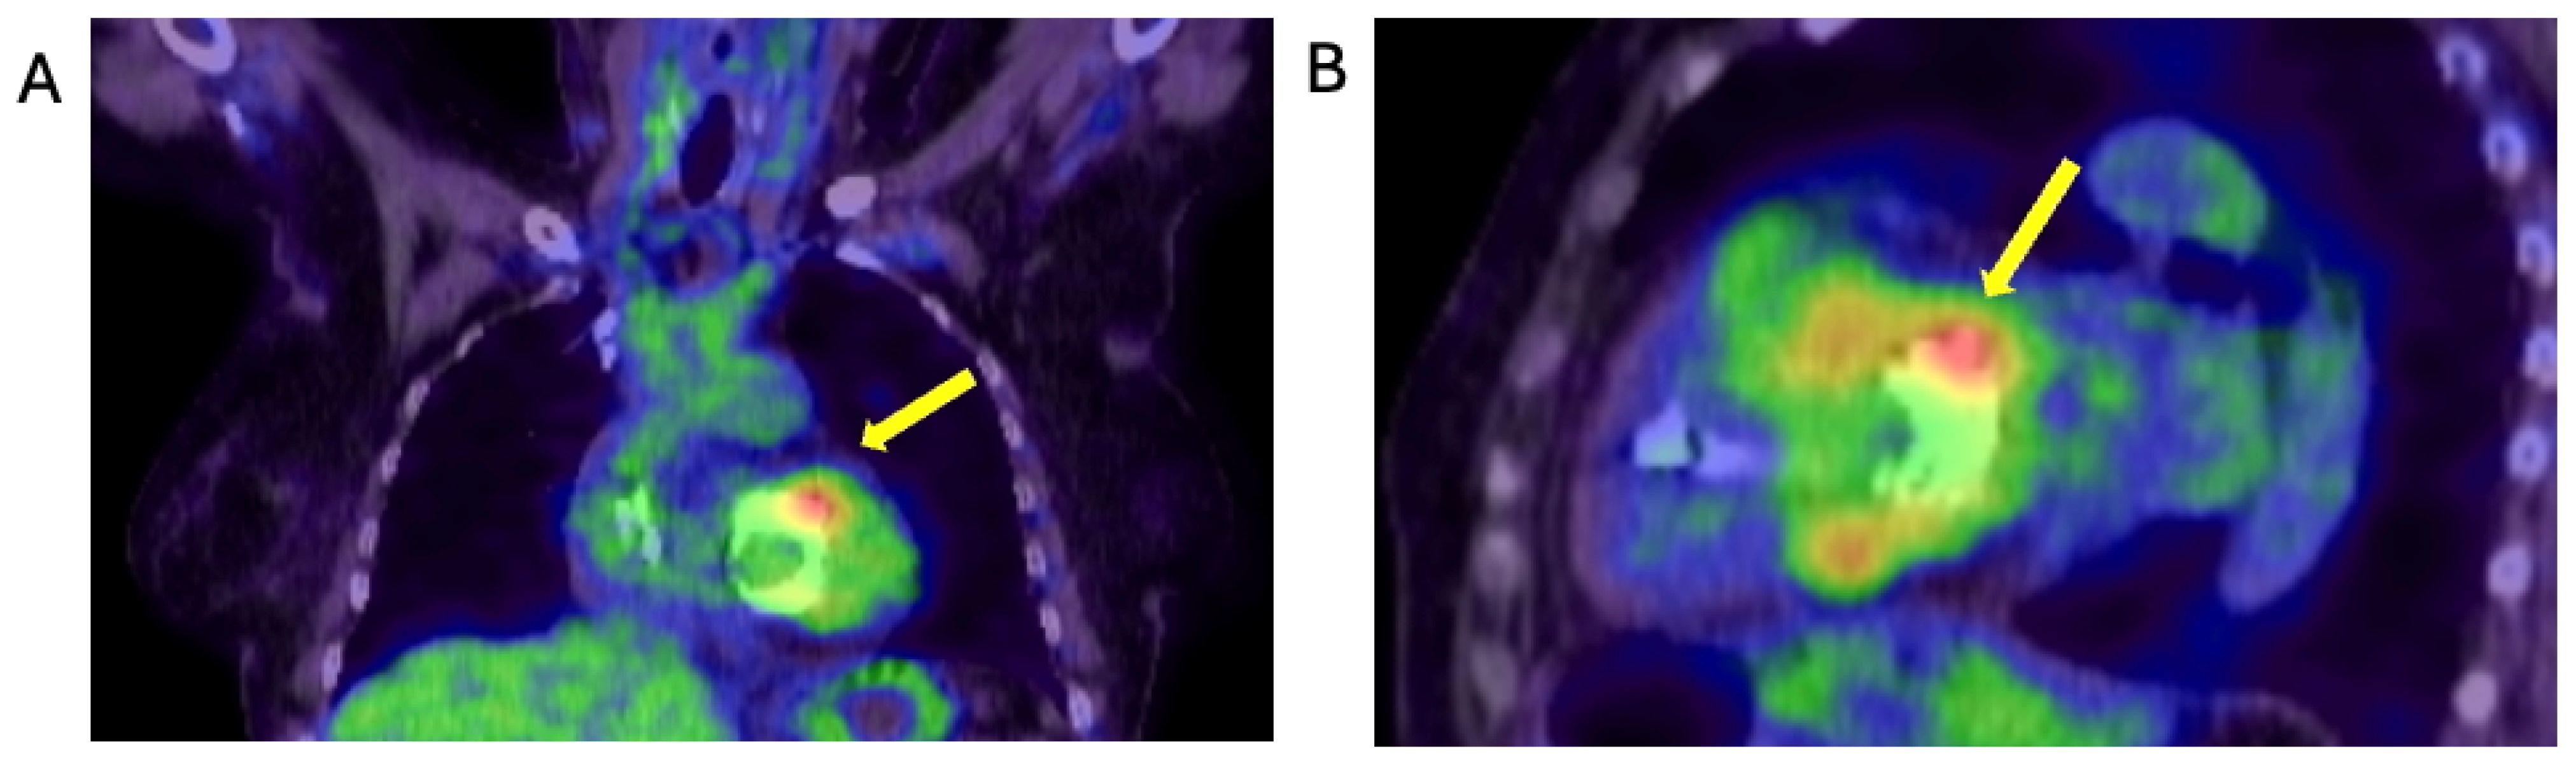

1.1.1. Case 1